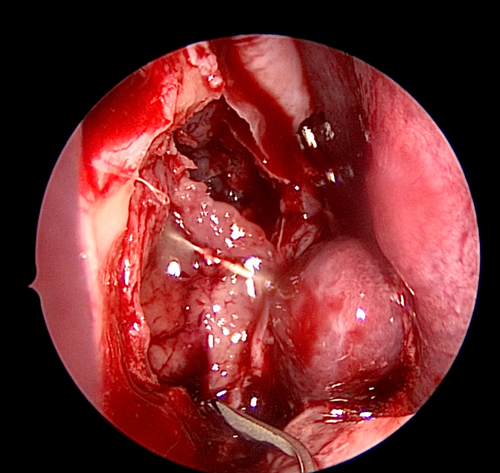

Figure 5. Inferior release of lacrimal sac.

The medial wall of the sac is tented medially using the end of the O’Donaghue probe and incised vertically using a sharp pointed Phaco knife at its most anterior aspect (see Figure 3). The aim is to create a large posterior based sac flap, which can later be folded back towards the uncinate process, facilitating full sac marsupialisation. Relieving incisions are then placed horizontally, both superiorly (see Figure 4) and inferiorly (see Figure 5) to complete the sac incision into a ‘C’ shape. The remaining posterior edge is left intact but the completed sac wall flap can now be folded posteriorly, exposing the entire sac lumen. The lacrimal probe should be visible and is pulled through with Mosquito artery forceps. The process is repeated with the probe and stent through the superior canaliculus. Upon delivery of the stents a Watzke sleeve is placed and the stents are tied. The lacrimal sac flaps remain folded backwards but the nasal mucosal flaps are repositioned to overlap each sac flap to encourage healing and ensure there is no exposed bone (see Figure 6).